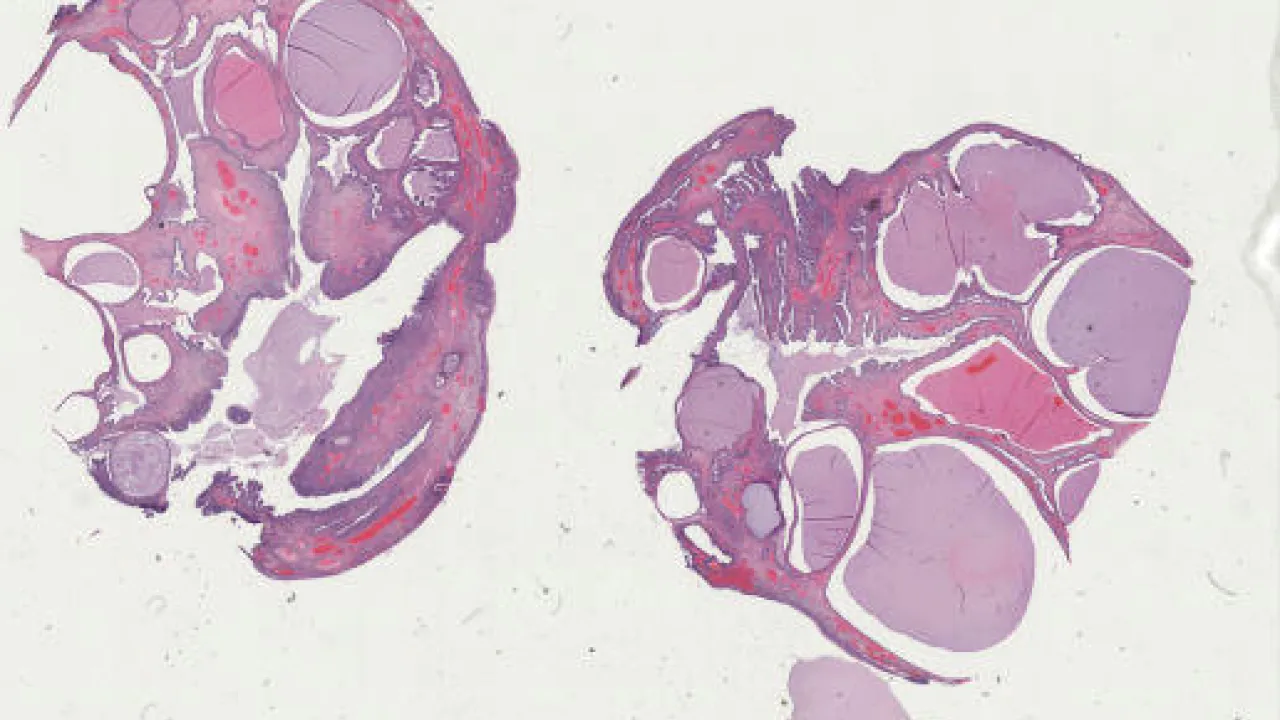

Ovary, Immature teratoma